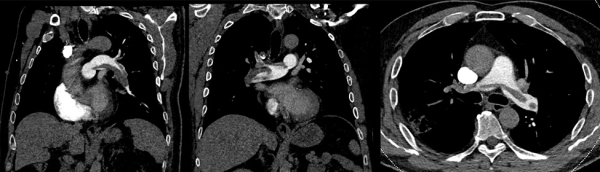

Imagerie : échographie transthoracique et scanner thoracique

(Vidéo 1, Figures 2 et 3)

- Volumineuse masse thrombotique proximale bilatérale « moulant » la carène

Figure 3 : angio - TDM thoracique initial